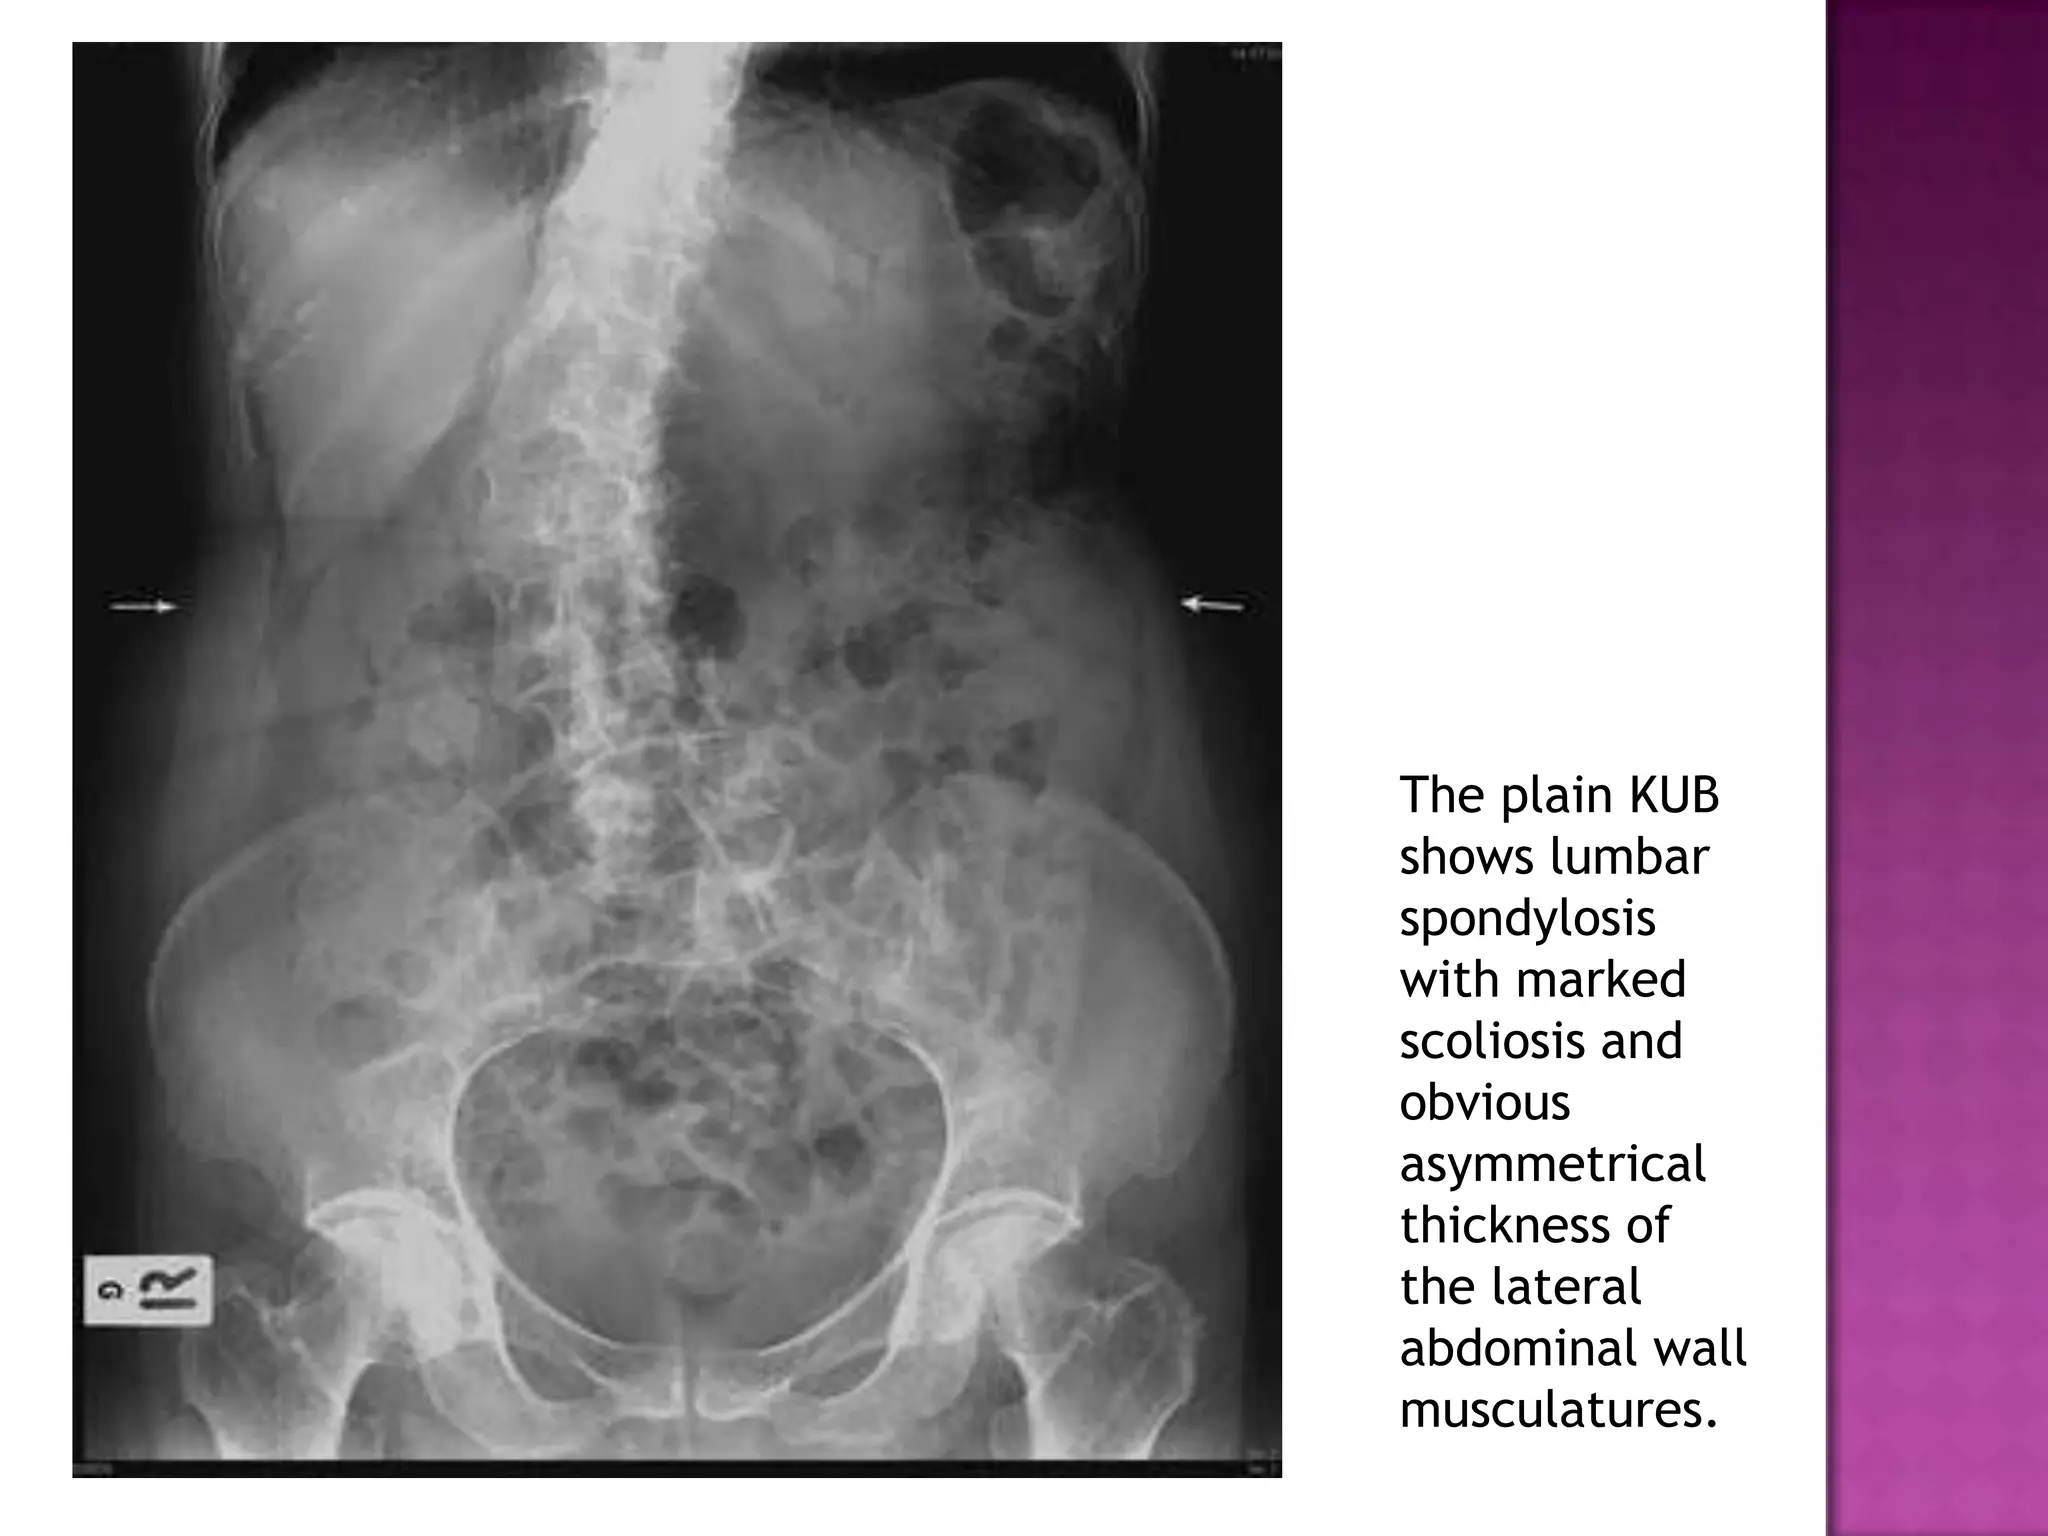

The plain KUB

shows lumbar

spondylosis

with marked

scoliosis and

obvious

asymmetrical

thickness of

the lateral

abdominal wall

musculatures.

The plain KUB showslumbar spondylosis with marked scoliosis and obvious asymmetrical thickness of the lateral abdominal wall musculatures.